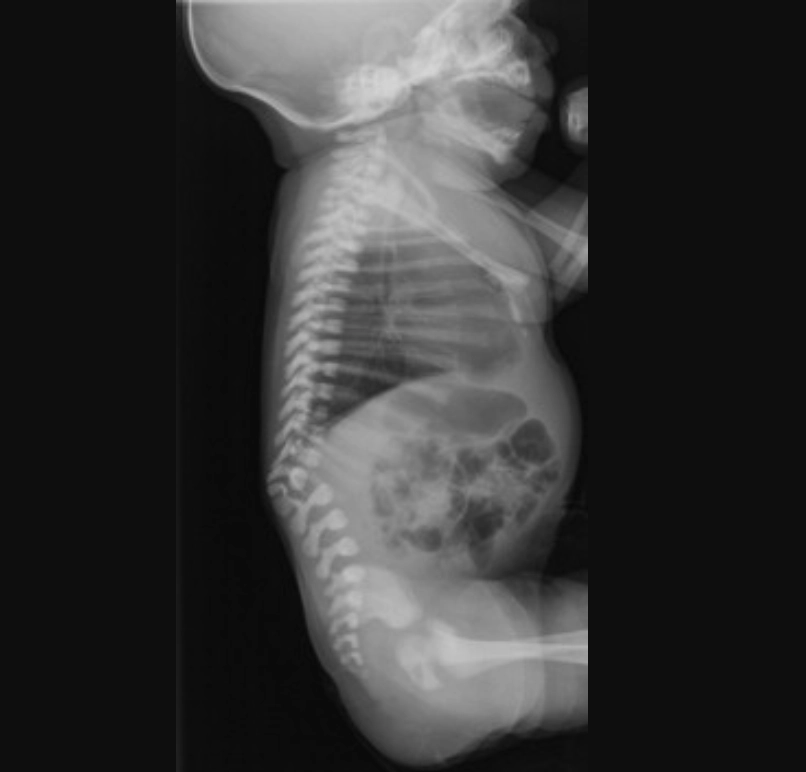

Thoái hóa cột sống bẩm sinh (Caudal Regression Sequence)

• Thoái hóa cột sống bẩm sinh (Caudal Regression Sequence)